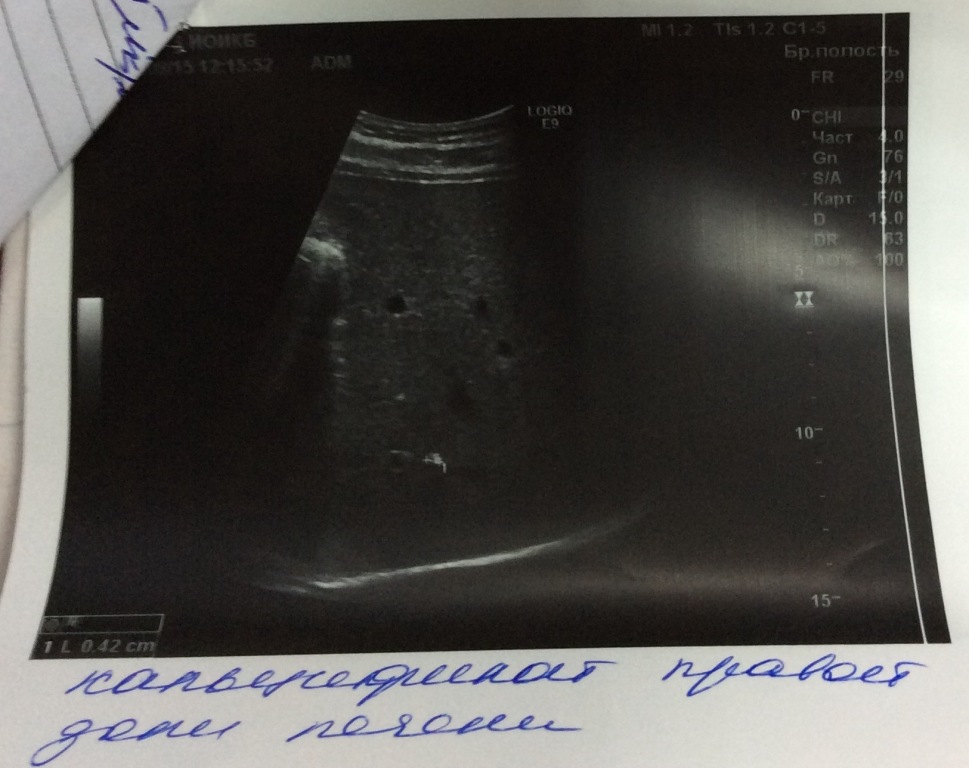

Дамы и Господа! Добрался до анализов. Вот, что есть сейчас на руках. Скоро еще будет интерлейкин 28 и подтип после 9 числа. Очень бы хотелось прочитать ваши комментарии и мнения. Спасибо.

И еще три анализа и иследования, которые не уместились в предыдущий пост.